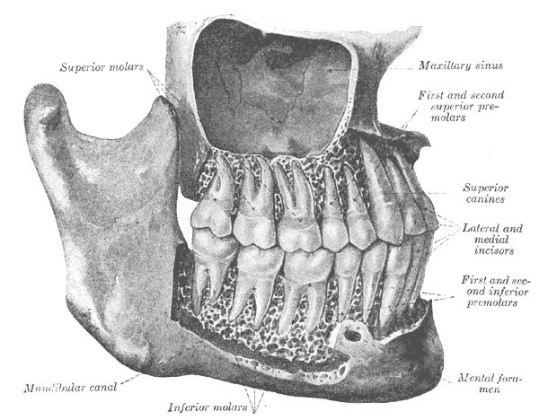

maxillary sinus anatomy

and dimensions

Usually, the largest of the sinuses

Pyramid-shaped cavity within the body of each maxilla

Volumetric space 15ml in average adult

Average dimensions: variation between people

* 37mm high

* 27mm wide

* 35mm antero-posteriorly

maxillary sinus and roots of maxillary teeth

Roots of maxillary molars and sometimes premolars may project into the floor of the maxillary sinus

The roots may perforate the bone so that only the mucosal lining of the sinus covers them